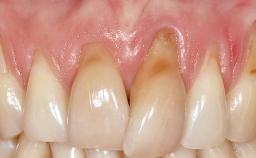

It is sometimes necessary to remove and replace compromised implants. This case is a clear example of the need for multiple steps to achieve an optimal therapeutic result for patients with non-salvageable implants. It illustrates how the lost soft and hard tissues were rebuilt in a sequence that improved the healing of the hard tissues and assured their long-term stability. The 35-year-old healthy patient presented with clinical attachment loss on the proximal and lingual surfaces of the natural dentition. Some gingival recession was present on natural teeth, particularly in the posterior sextants (S1, S3, S4, and S6).